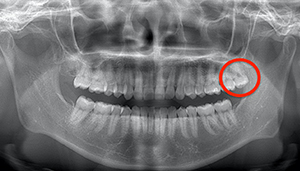

- 抜歯前写真(レントゲン)

| 抜歯内容 | 左下親知らずが横向きになって半分埋まっている状態だったため、麻酔を行い、親知らずの奥の歯ぐきに切開をいれ、歯が囲んでいる骨を削り、歯の頭の部分を削って出し、その後根の部分に器具をかけて抜歯しました。 親知らずが一部神経に近い部分があったため、術後に麻痺が出る可能性がありました。このケースでは事前にCTを撮影し、歯の位置、根の方向、神経との距離を確認していたため、幸い麻痺が出ることはありませんでした。 術後1週間経過して糸取りをして治療は終了となりました。抜歯後3日間は腫れと痛みで大変だったが、糸取りをする頃には痛みも腫れも無くなったと患者さまも喜んでおられました。 |